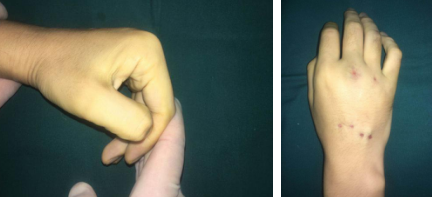

于是,刘先生辗转来到我院,正逢手外二熊祖国医生坐门诊。熊医生看完片子,告诉他可以微创手术,而且术后手功能基本恢复正常。刘先生一听很高兴,希望能尽快安排手术。熊医生为其采用的治疗方案为闭合复位经皮微创克氏针内固定,既能很好地固定骨折,还不留疤痕,早期通过功能锻炼,达到恢复功能。熊医生和吴衡医生团队很快做完了手术,术后第二天刘先生就出院了。

术中

出院时,针对他的伤情,专门制定了刘先生复诊时间及根据恢复情况循序渐进进行指导功能锻炼,刘先生的手终于恢复正常了,骨头长好了,钉子也取出来了。刘先生看到自己现在的手感慨万千,一方面非常后悔一时冲动伤害了自己,另一方面又感觉很幸运,遇到了两位好医生,不然自己真得可能会因此放弃热爱的事业。

内固定取出后

熊医生介绍,刘先生术前右手不能握拳,伸不直,伸屈都有影响,术后功能基本恢复正常。